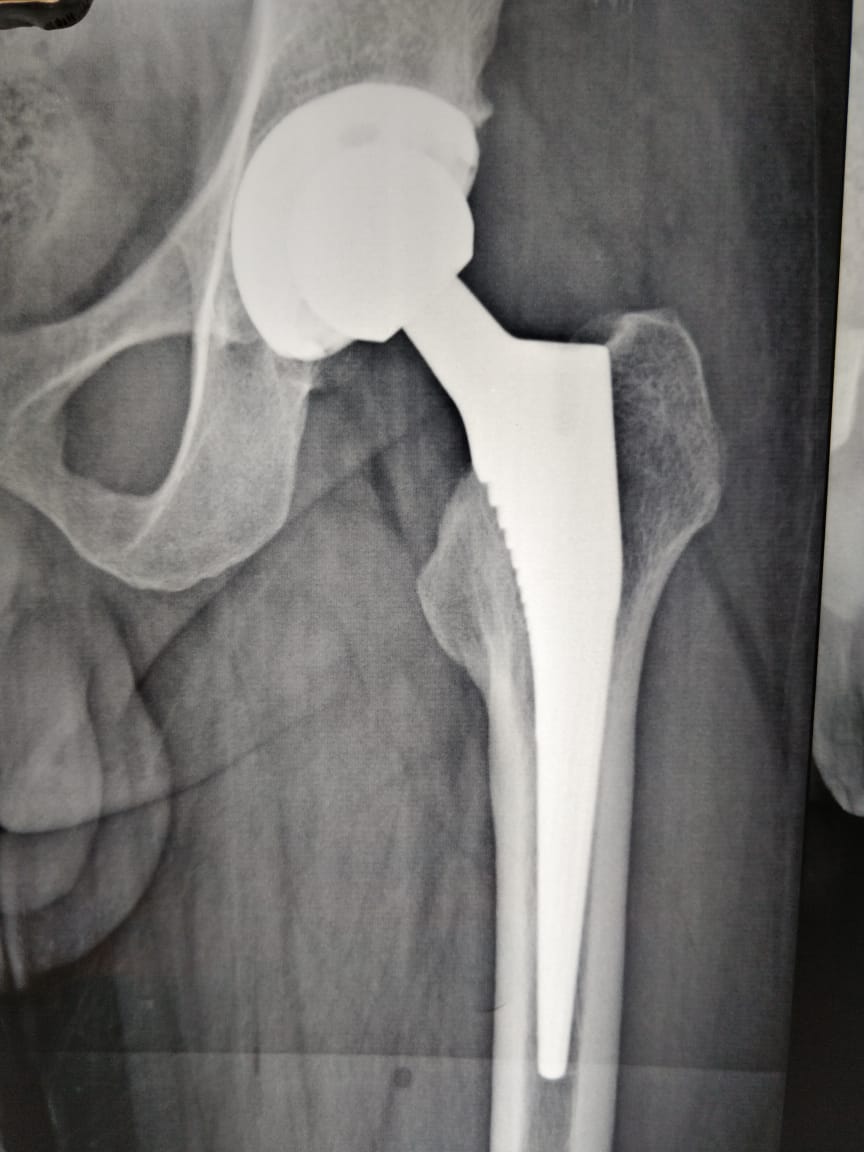

Dr. Nilesh Hirekhan Orthopedic specializes in orthopedic surgery with a focus on joint replacement, sports medicine, and trauma surgery.